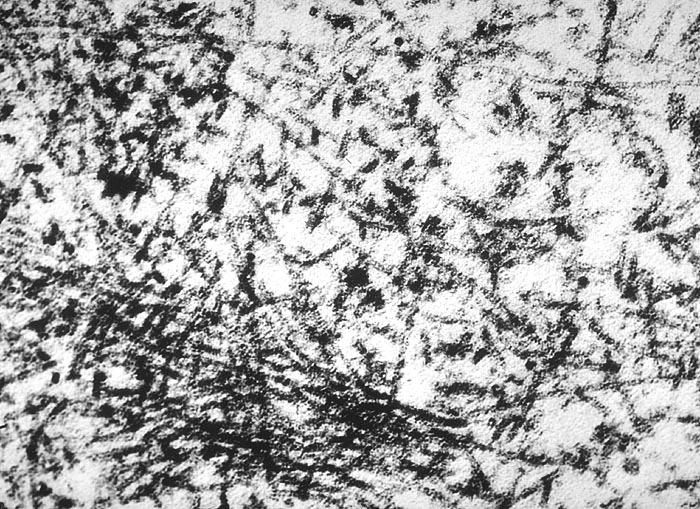

PathoPic ID 2041 - Amyloidfibrillen

Amyloidfibrillen

Systemerkrankung/Immunpathologie

Niere

Niere, Harnwege

Starke Vergrösserung von irregulär angeordneten, unterschiedlich langen Amyloidfibrillen von 8nm Dicke.

EM